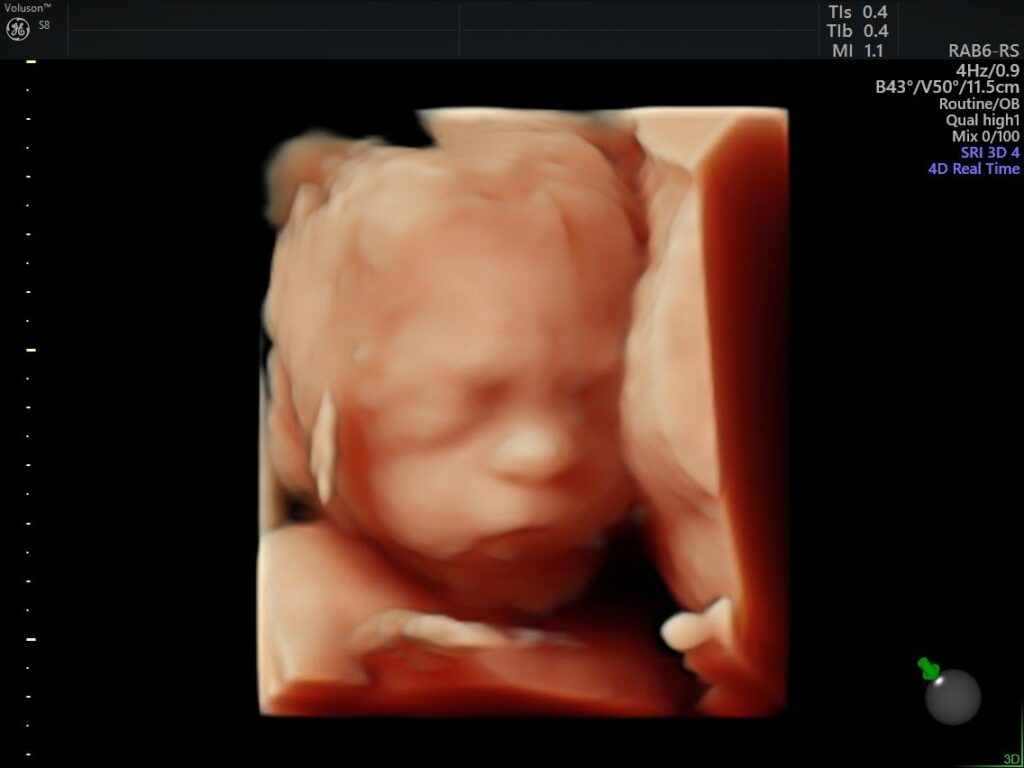

Ejemplos Ultrasonido: 4a Dimensión